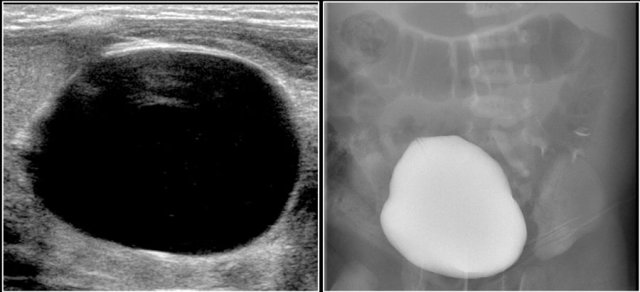

Antenatally a duplex system of the left kidney was diagnosed with hydronephrosis. A postnatal ultrasound demonstrates a large cyst in the upper pole of the left kidney and some smaller cysts (not shown).

No normal parenchyma was visible.

On MCUG reflux in the lower pole system is seen, which is displaced caudally and rotated due to the upper pole mass.

This is probably a MCKD confined to the upper pole.

MCKD can affect one pole of a duplicated pelvicocalyceal system.